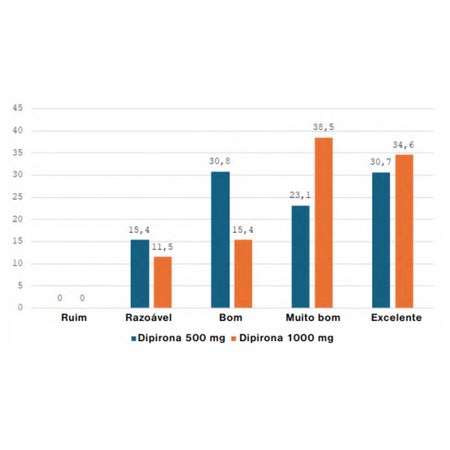

Objetivo: O objetivo desse estudo foi avaliar se há benefício em aumentar a dose da dipirona 500mg para 1.000mg quando coadministrada com a nimesulida, em cirurgia de terceiros molares inferiores. Métodos: Foi realizado um ensaio clínico randomizado, de amostras dependentes, triplo-cego, pelo método split-mouth. Os pacientes foram submetidos a dois procedimentos em tempos distintos, e receberam as medicações após randomização e alocação em: grupo A (dipirona 500mg + nimesulida...

Objective: The aim of this study was to assess whether there is a benefit in increasing the dose of dipyrone from 500mg to 1,000mg when co-administered with nimesulide, in lower third molar surgery. Methods: A randomized clinical trial of dependent samples, triple-blind, was carried out using the split-mouth method. The patients underwent two procedures at different times, and received the medications after randomization and allocation into: group A (dipyrone 500mg + nimesulide 100mg) or...